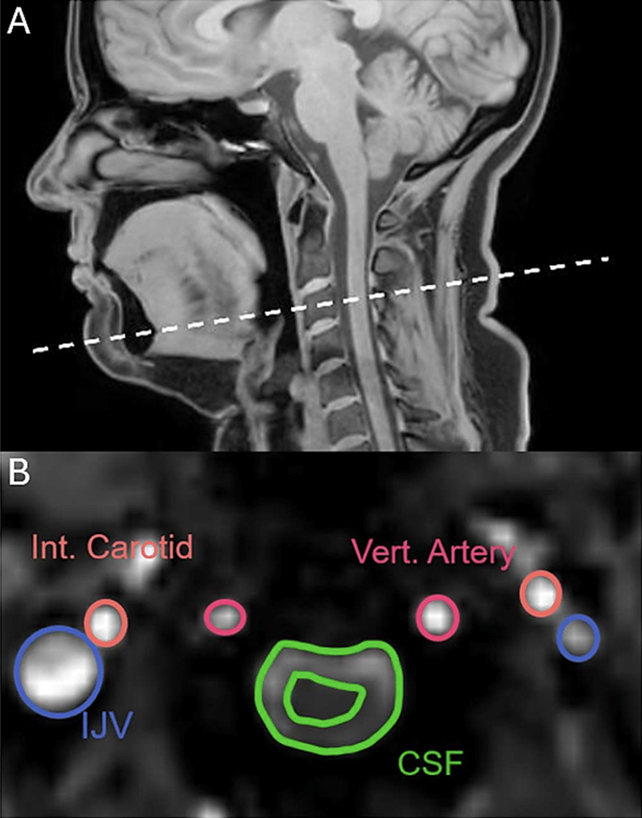

Οι επιστήμονες χρησιμοποίησαν μαγνητική τομογραφία σε 22 υγιείς εθελοντές. Κατά τη διάρκεια των σαρώσεων οι συμμετέχοντες κλήθηκαν να χασμουρηθούν, να πάρουν βαθιές αναπνοές, να καταστείλουν το χασμουρητό και να αναπνεύσουν φυσιολογικά.

Η ανάλυση έδειξε επίσης ότι τόσο το χασμουρητό όσο και οι βαθιές αναπνοές αυξάνουν τη φλεβική απορροή αίματος από τον εγκέφαλο. Αυτό δημιουργεί περισσότερο διαθέσιμο χώρο ώστε να εισρεύσει φρέσκο αίμα.

Στα αρχικά στάδια του χασμουρητού καταγράφηκε και σημαντική αύξηση της ροής από την καρωτιδική αρτηρία προς τον εγκέφαλο, περίπου κατά ένα τρίτο. Αντίθετα, η κατεύθυνση της ροής του αίματος δεν αντιστρέφεται όπως συμβαίνει με το εγκεφαλονωτιαίο υγρό.